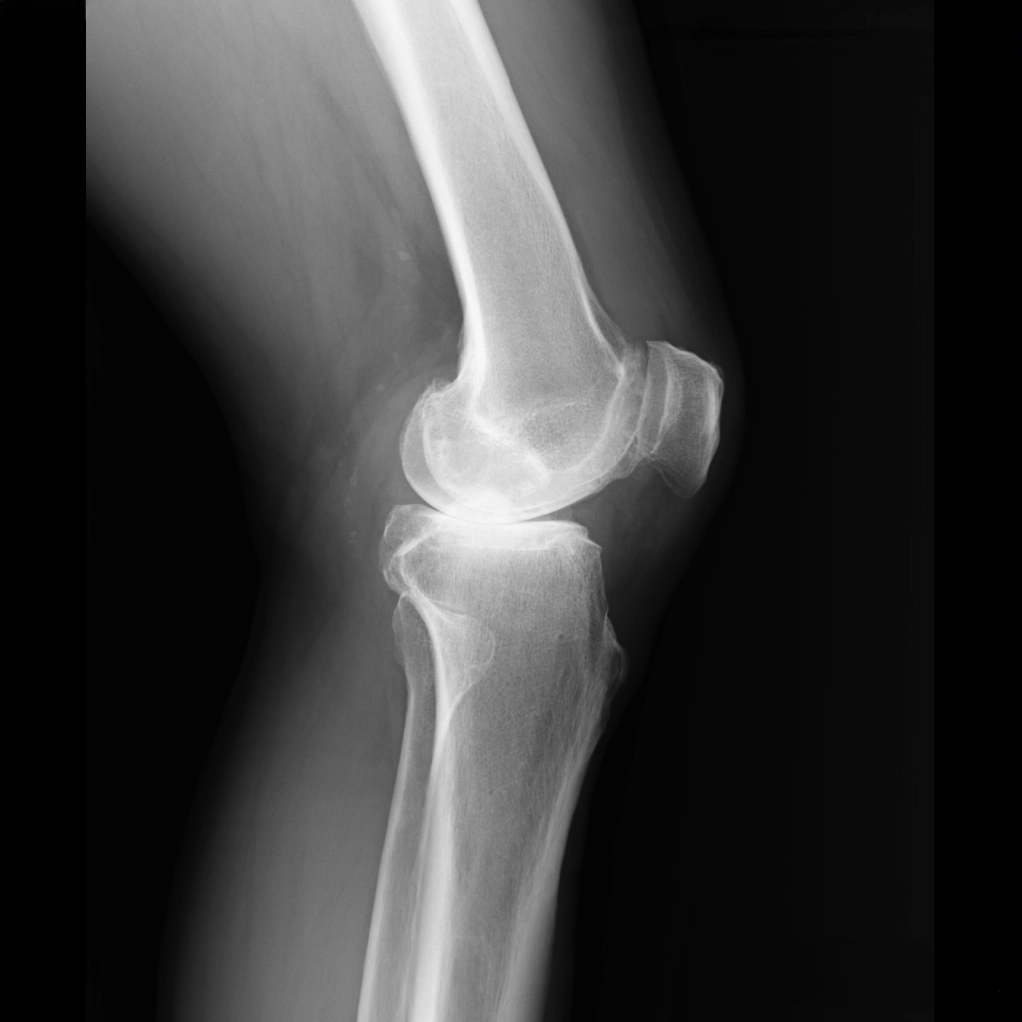

ひざ関節は、大腿骨と脛骨の間の隙間の部分です。レントゲンではこの部分が隙間として写りますが、実際には関節軟骨と半月板が存在します。立位で体重をかけて撮影した場合、この隙間の広さがおおよそ関節軟骨の厚みを示すと考えてよいでしょう。この大腿骨と脛骨の隙間のうち、腓骨に近い側を外側関節、腓骨から遠い側を内側関節と呼びます。また、脛骨の中央には2つの小さな山のような部分が見えますが、ここには前十字じん帯と後十字じん帯がついています。

O脚変形がみられる場合、初期のレントゲンでは外側関節に比べて内側関節の隙間がやや狭くなっています。これは内側の軟骨が少し減ってきた状態を示しています。

上のレントゲン写真の患者さんは76歳、左ひざ中期の方です。内側の軟骨はほとんど失われ、低い椅子から立ち上がるたびにギリギリと音がして激痛が生じていました。そこで、体重をかけずに椅子に座り、ひざから下をぶらぶらと振る「足放り体操」をはじめていただきました。関節液が残った軟骨を潤し、軟骨が失われた部分には線維軟骨が少しずつ覆うようになります。

ただし、この状態で体重をかけて歩くと、ひざの内側に体重の約5倍の力が加わり、せっかく作られた軟骨もすぐにすり減ってしまいます。だからこそ、歩き方を変える必要があるのです。